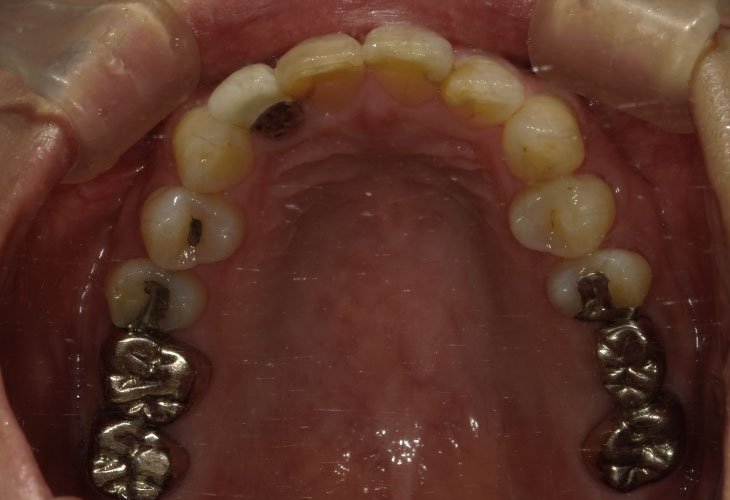

下顎臼歯部インプラント治療(2本)

主訴 右下奥歯の歯が無い。インプラント治療をしたい。

右下臼歯部欠損

治療内容 インプラント(右下6・7)

オールセラミックス(左上2)

E-MAX CAD(左上6・7)